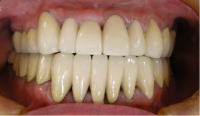

アフター2枚

(きれいに並んだ上下の白い歯。口元に自信が回復しました。)

治療終了時の歯型模型(正面観)

補綴治療終了時のX線写真(全ての歯の神経の治療を終えて

補綴治療をしました。)

保存するには厳しい状態の歯もありましたが、

何とか全ての歯を抜かずに治療を終了することができました。

あとはメンテナンスでしっかり管理していき、

問題が起これば速やかに対応をしてゆきます。